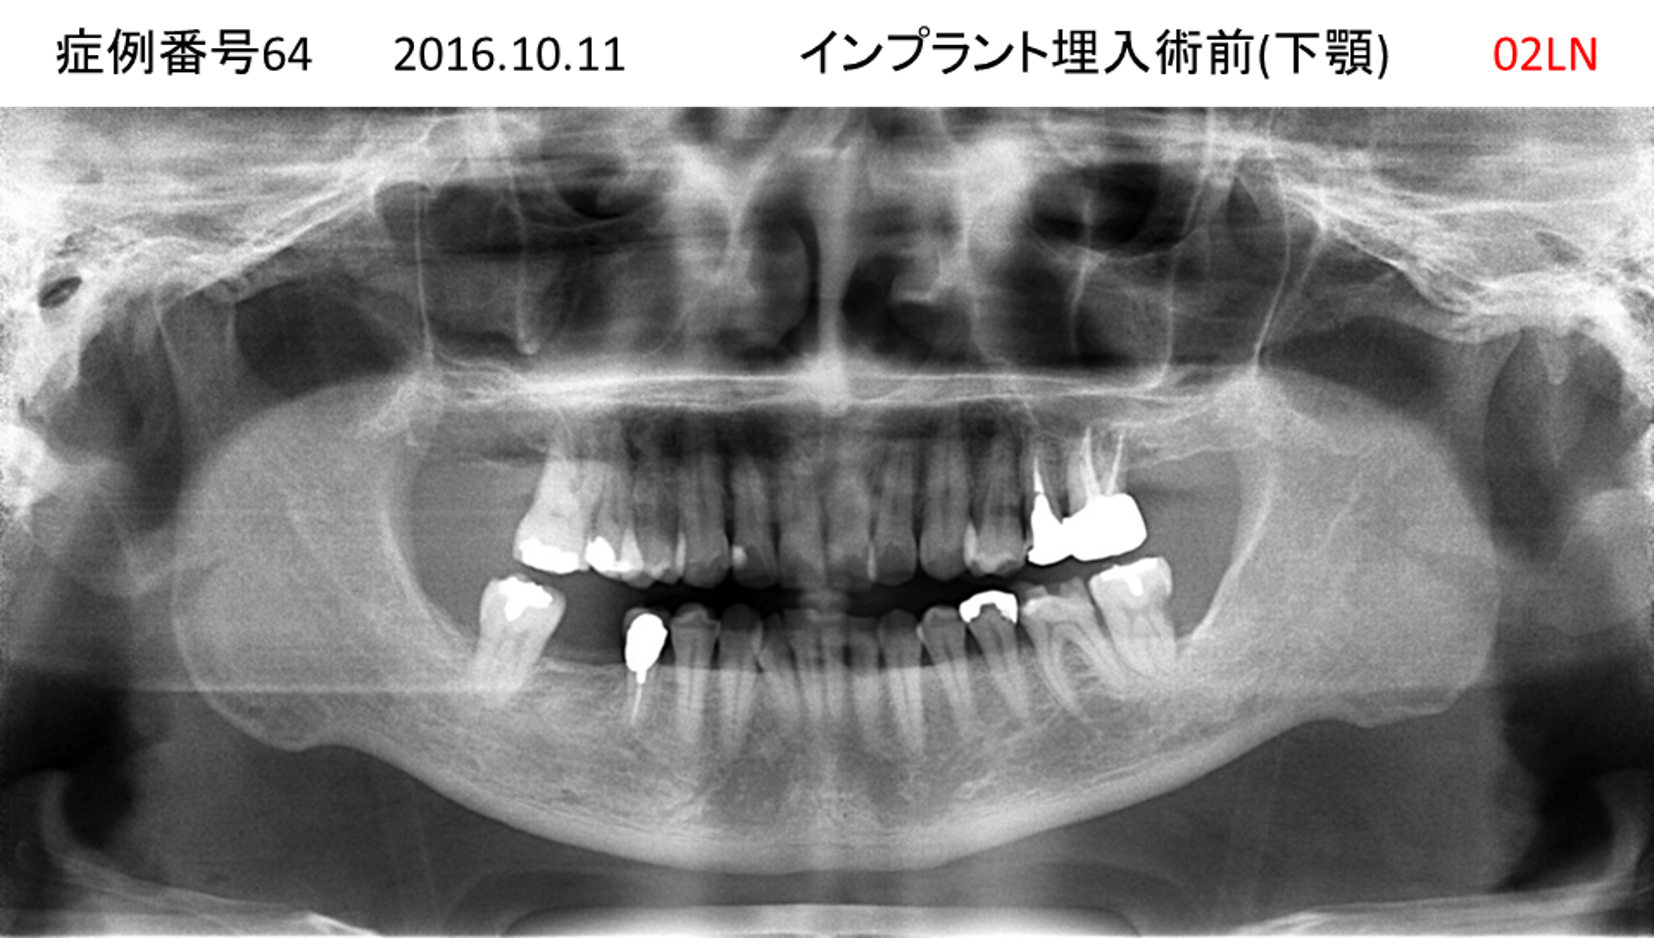

左下の歯が痛い患者様のインプラント症例

| 治療名称 |

インプラント |

| 治療費用 |

330万円+税 |

| 治療期間 |

4か月 |

| 患者さんの症状(主訴) |

左下の歯が痛い |

| 治療内容 |

サイナスリフト 抜歯即時インプラント |

| 治療結果 |

食事に困らない。見た目がとても良くなった。 |

| 治療の注意点(リスク/副作用) |

インプラントが壊れたら再治療が必要 |